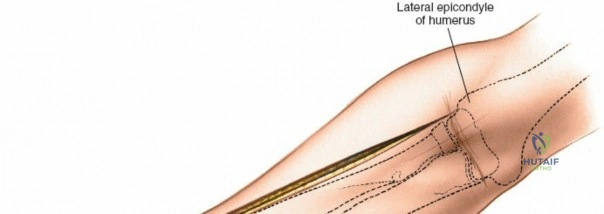

Accurate identification of surface landmarks is the first step in a successful Henry approach. Palpate the biceps tendon, a stout, taut structure crossing the anterior elbow joint just medial to the brachioradialis muscle. Next, palpate the brachioradialis itself, the fleshy muscle forming the lateral border of the cubital fossa. Finally, identify the styloid process of the radius distally. Note that when the forearm is fully supinated (the anatomic position), the radial styloid is truly lateral.

Make a straight or gently curved incision beginning at the anterior flexor crease of the elbow, just lateral to the biceps tendon. Extend this incision distally toward the styloid process of the radius. The exact length and placement of the incision are dictated by the specific pathology; the approach is highly modular, and often only the proximal, middle, or distal third of the incision is required.

Retractor Placement and Fixation Technique

Once the proximal radius is exposed, great care must be taken with retractor placement. Never place Hohmann or levering retractors blindly around the posterior surface of the radial neck. Because the PIN may touch the bone posteriorly in up to 25% of patients, a posteriorly placed retractor can easily crush the nerve against the radial cortex. Instead, use gentle right-angle retractors or place retractors only on the anterior and lateral aspects of the bone, utilizing the elevated supinator as a shield.

For fracture fixation, a dynamic compression plate or locking compression plate is applied to the volar surface of the radius. The volar surface provides a flat, mechanically advantageous surface for plating and allows for excellent soft tissue coverage by the overlying muscle bellies upon closure. Ensure that the natural radial bow is meticulously restored during reduction to guarantee full postoperative pronation and supination.